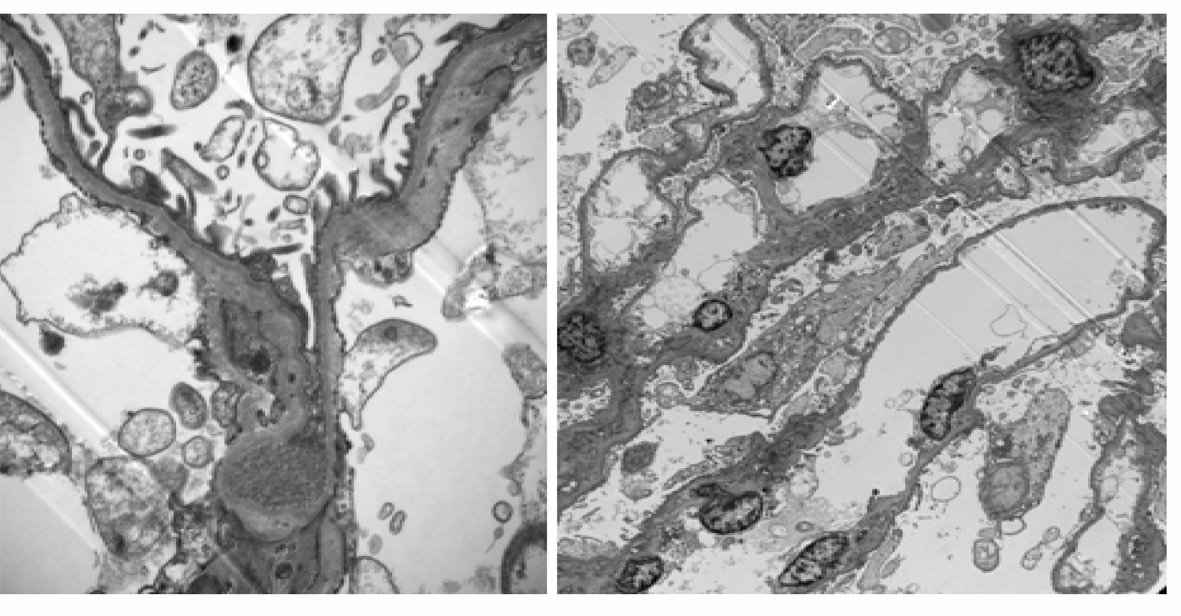

Thin Basement Membrane Disease And Pregnancy : Thin Basement Membrane Diseases - The Best Picture ... / Thin basement membrane disease (tbmd) (also called benign familial hematuria) is a congenital glomerulopathy characterized by thinning (<250 nm) of the glomerular basement membrane.. Basement membrane disease acute tubular necrosis host defense mechanisms bladder neck obstruction chronic renal failure. Alport syndrome is a disorder of the glomerular basement membrane resulting in glomerular hematuria. Thin basement membrane nephropathy (tbmn) is characterized by persistent hematuria and thinning of glomerular basement membrane. Karl tryggvason and jaakko patrakka. Thin basement membrane disease (tbmd, also known as benign familial hematuria and thin basement membrane nephropathy or tbmn) is, along with iga nephropathy, the most common cause of hematuria without other symptoms.

Thin basement membrane disease, or benign familial hematuria, is an autosomal dominant basement membrane glomerulopathy. Hereditary, often autosomal dominant disorder of thinning of lamina dense of glomerular basement membrane; Thin basement membrane disease (tbmd) (also called benign familial hematuria) is a congenital glomerulopathy characterized by thinning (<250 nm) of the glomerular basement membrane. Thin basement membrane nephropathy (tbmn) is the most common cause of persistent glomerular hematuria. Those patients who carry homozygous or compound. Thin basement membrane disease or benign familial hematuria is manifested by persistent microscopic hematuria, minimal proteinuria, and the absence of ear or eye involvement. Thin basement membrane disease (tbmd, also known as benign familial hematuria and thin basement membrane nephropathy or tbmn) is, along with iga nephropathy, the most common cause of hematuria without other symptoms. Women with chronic kidney disease (ckd) may commence pregnancy with increased protein excretion as a result of their underlying disease. In contrast, glomerulocystic kidney disease (gckd) is a rare disease, associated with slow progressive renal dysfunction. Basement membranes basement membrane thickening synovial capillaries rheumatoid arthritis endothelial cells this is a preview. The glomerular basement membrane (gbm) is a specialized structure with a significant role in maintaining the glomerular filtration barrier. Patients with this condition will have normal kidney function. However, only limited studies address the prognosis.

The glomerular basement membrane (gbm) is a specialized structure with a significant role in maintaining the glomerular filtration barrier. Sometimes, blood may appear in your urine. Thin basement membrane disease or benign familial hematuria is manifested by persistent microscopic hematuria, minimal proteinuria, and the absence of ear or eye involvement. A series of 28 cases. Increased global sclerosis, with later development of hypertension and renal insufciency in the 20. Thin basement membrane nephropathy (tbmn) is characterized by persistent hematuria and thinning of glomerular basement membrane. Thin basement membrane nephropathy (tbmn) is the most common cause of persistent glomerular hematuria. Thin basement membrane disease with heavy proteinuria or nephrotic syndrome at presentation.

Thin basement membrane disease with heavy proteinuria or nephrotic syndrome at presentation. Thin glomerular basement membrane disease / lesion. It is a rare disorder that has been diagnosed in less than 1 percent of the population. Thin basement membrane nephropathy (tbmn) is the most common cause of persistent glomerular hematuria. Thin glomerular basement membrane disease: However, only limited studies address the prognosis. In a study from 2005, records. The glomerular basement membrane (gbm) is a specialized structure with a significant role in maintaining the glomerular filtration barrier. Thin basement membrane disease (tbmd) (also called benign familial hematuria) is a congenital glomerulopathy characterized by thinning (<250 nm) of the glomerular basement membrane. Thin basement membrane disease is a benign kidney condition that results in the thinning of the tissue in the glomeruli, structures in your body which are responsible for filtering your blood. Increased global sclerosis, with later development of hypertension and renal insufciency in the 20. It has been estimated to affect up to 1% of the general population; Thin basement membrane nephropathy basement membrane disease familial hematuria benign familial hematuria anterior lenticonus.